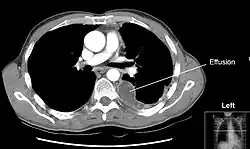

Компьютерная томограмма, демонстрирующая избыточный объём жидкости в левой плевральной полости (гидроторакс). Висцеральный и париетальный листки плевры утолщены.

В области корней лёгких париетальная плевра, прилегающая к средостению (медиастинальная плевра), переходит в висцеральную плевру. В свою очередь, соединительная ткань, формирующая висцеральную плевру, проникает в ткань лёгких, образуя интерстициальный лёгочный каркас, а также выстилает поверхности долей лёгких в междолевых щелях. Плевра, выстилающая боковые поверхности грудной полости (рёберная плевра) и медиастинальная плевра внизу переходят на поверхность диафрагмы, образуя диафрагмальную плевру. Места перехода плевры с одной поверхности лёгкого на другую называются плевральными синусами; они не заполняются лёгкими даже при глубоком вдохе. Различают рёберно-диафрагмальные, рёберно-медиастинальные и диафрагмально-медиастинальные синусы, ориентированные в различных плоскостях. В плевральных синусах, особенно самых низкорасположенных задних рёберно-диафрагмальных, в первую очередь накапливается жидкость при развитии гидроторакса (см. рисунок). Иннервируется плевра блуждающими, межрёберными и диафрагмальными нервами. В париетальной плевре располагаются болевые чувствительные рецепторы.